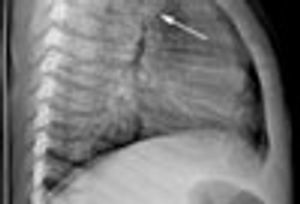

Sharp, shooting posterior neck pain prompted a 29-year-old man to seek medical attention. The pain began 4 days earlier and progressed to the point that it occurred with swallowing. He wore a wool scarf to restrict his cervical range of motion. During the history taking, he remained rigid and avoided rotation and flexion or extension of the spine.